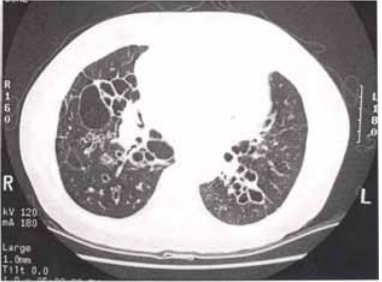

53 一位 48 歲之男性患者有抽菸史,長期咳嗽且多黃痰已有多年,胸部之電腦斷層攝影檢查顯示如圖, 請問其最可能之診斷為下列何者?

(A) 慢性支氣管炎 (B)肺膿瘍 (C)支氣管擴張症 (D)肺氣腫